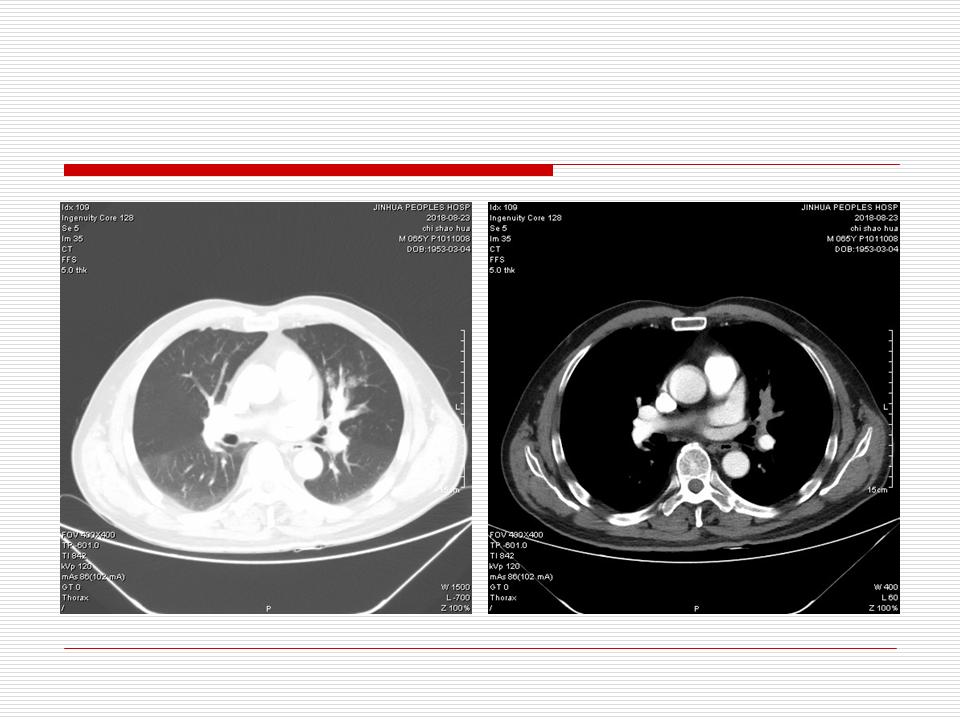

肺部阴影永恒且最重需要鉴别的是:到底是炎症还是肿瘤?但临床的病例中的影像表现难以界定或有些肿瘤特征,同时又有些炎症特点是非常常见的情况。作为临床医生我们怎么去总结分析,并找到之所以是炎症或之所以是肿瘤的细微差别或特点非常重要,也非常有用。2019.12.7浙江省2019年胸心外科学学术年会在宁波召开时,我的临床病例分析与经验总结<那些像肺癌的炎症与像炎症的肺癌>获得在大会交流的机会,以下为该PPT的内容,与你分享,希望对同道有益,有借鉴与启迪。若有探讨与进一不完善的建议,欢迎文末留言讨论: